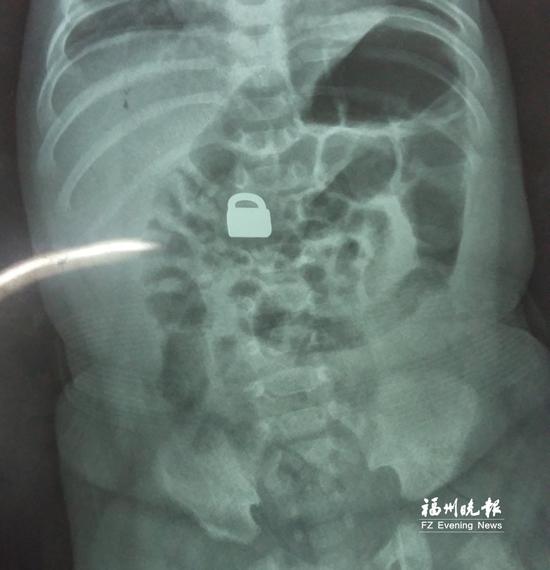

“X光片显示,那是一把1.5厘米×0.9厘米的平安锁,有指甲盖大小,已经到了宝宝的小肠处。”7月28日,陈惠萍见到宝宝时,吃了一惊,“他真的好小,被抱在妈妈怀里,眼睛微微睁开,我估计他的世界还是混沌的,没想到就已经接受了这么大的挑战。”